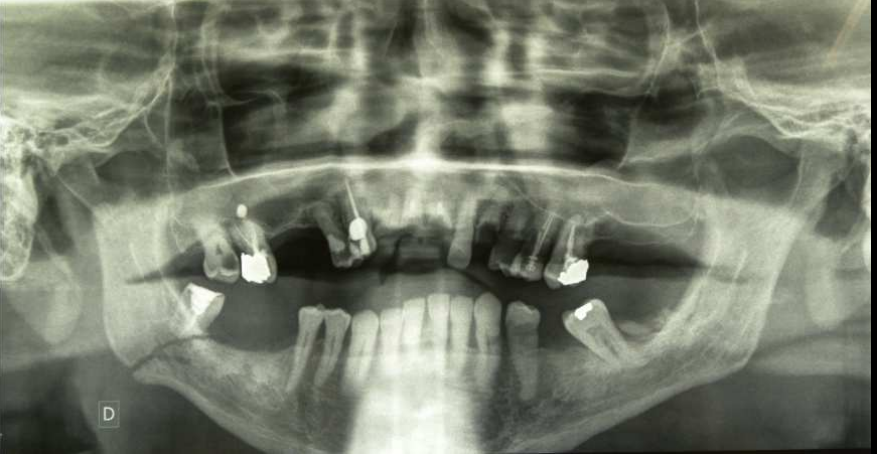

Comment vous définiriez la fracture au niveau de la dent ?

Fracture de la portion dentée mandibulaire?

Sur mon truc de conf Khalifa ils disent que c'est une fracture de l'angle, mais pour moi un fracture de l'angle c'est forcement après la portion dentée mais je suis loin d'être un expert en chirurgie ORL.

Fracture de l'angle mandibulaire non ?

J'aurais dit pareil mais j'ai tenté comme il l'a posté ici ça sentait la couille